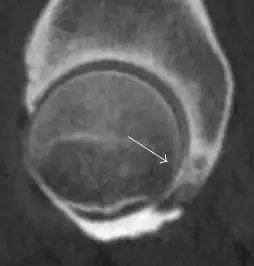

Most of the angles and measurements described in the plain radiograph section can be accurately reproduced on MRI. In addition, the superiority of MRI resolution with intra-articular contrast allows detection of labral and chondral abnormalities that may influence the choice of medical, percutaneous, or surgical management (Figure 9).[1]

Figure 9:

-

Sagittal T1 weighted image showing anterosuperior labral tear.[1] -

Sagittal T1 weighted image showing chondral lesion.[1] -

Sagittal CT-arthrography showing posteroinferior chondral injury.[1] -

Coronal CT-arthrography (d) showing ligamentum teres tear.[1]

MR arthrography has proven superior in accuracy when compared to native MR imaging. It is considered the best technique to assess the labrum. Knowledge of the normal variable morphology of the labrum helps to differentiate tears from normal variants. A triangular shape is most commonly seen in 66% of asymptomatic volunteers, but round, flattened, and absent labra can also be found in asymptomatic populations. MR arthrography has demonstrated sensitivity over 90% and specificity close to 100% in detecting labral tears. Loose bodies are demonstrated as filling defects surrounded by the hyperintense gadolinium.[1]

Association between labral tears and chondral damage has been demonstrated. This underscores the interaction between cartilage and labrum damage in the progression of osteoarthritis. Chondral damage to the posteroinferior part of the acetabulum as a contrecoup lesion occurs in approximately one-third of pincer cases secondary to persistent abutment on the anterior part of the joint leading to a slight posteroinferior subluxation. This is considered a bad prognosis sign.[1]

MR arthrography can also demonstrate ligamentum teres rupture or capsular laxity, which are debated causes of microinstability of the hip. Elongation of the capsule or injury to the iliofemoral ligament or labrum may be secondary to microtrauma in athletes. MR can demonstrate abnormalities in these cases, such as increased joint volume or a ligamentum teres tear (Figure 9).[1]